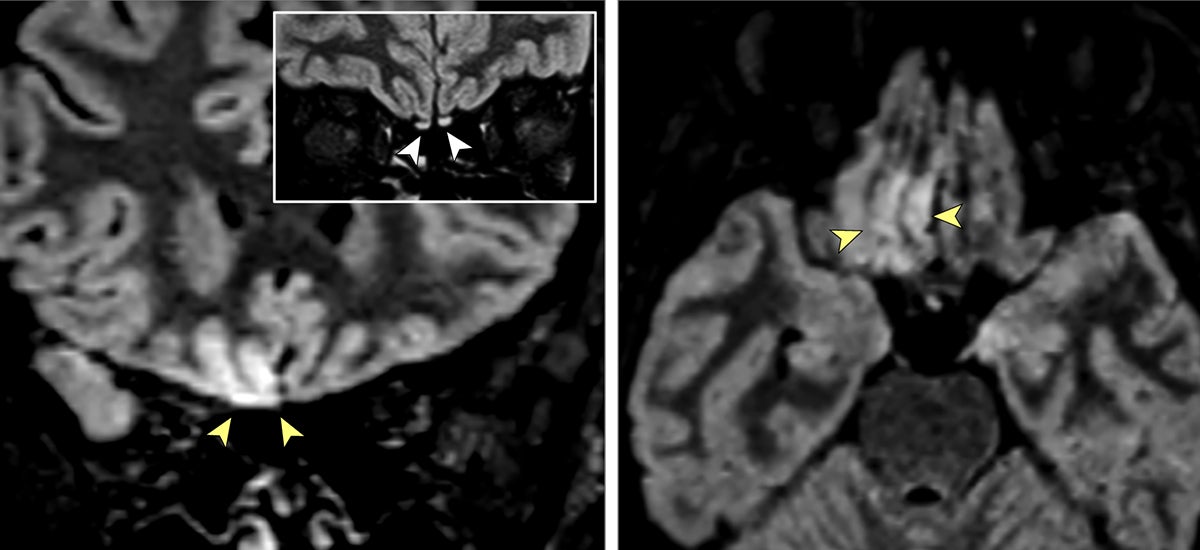

Una radiologa italiana se ha convertido en el primer caso conocido en el que un paciente de covid-19 sufre alteraciones cerebrales debido a la invasión del cerebro por parte del patógeno. No, por el momento no hay que temer una invasión zombie, pero el caso sirve para explicar uno de los síntomas más desconcertantes de…